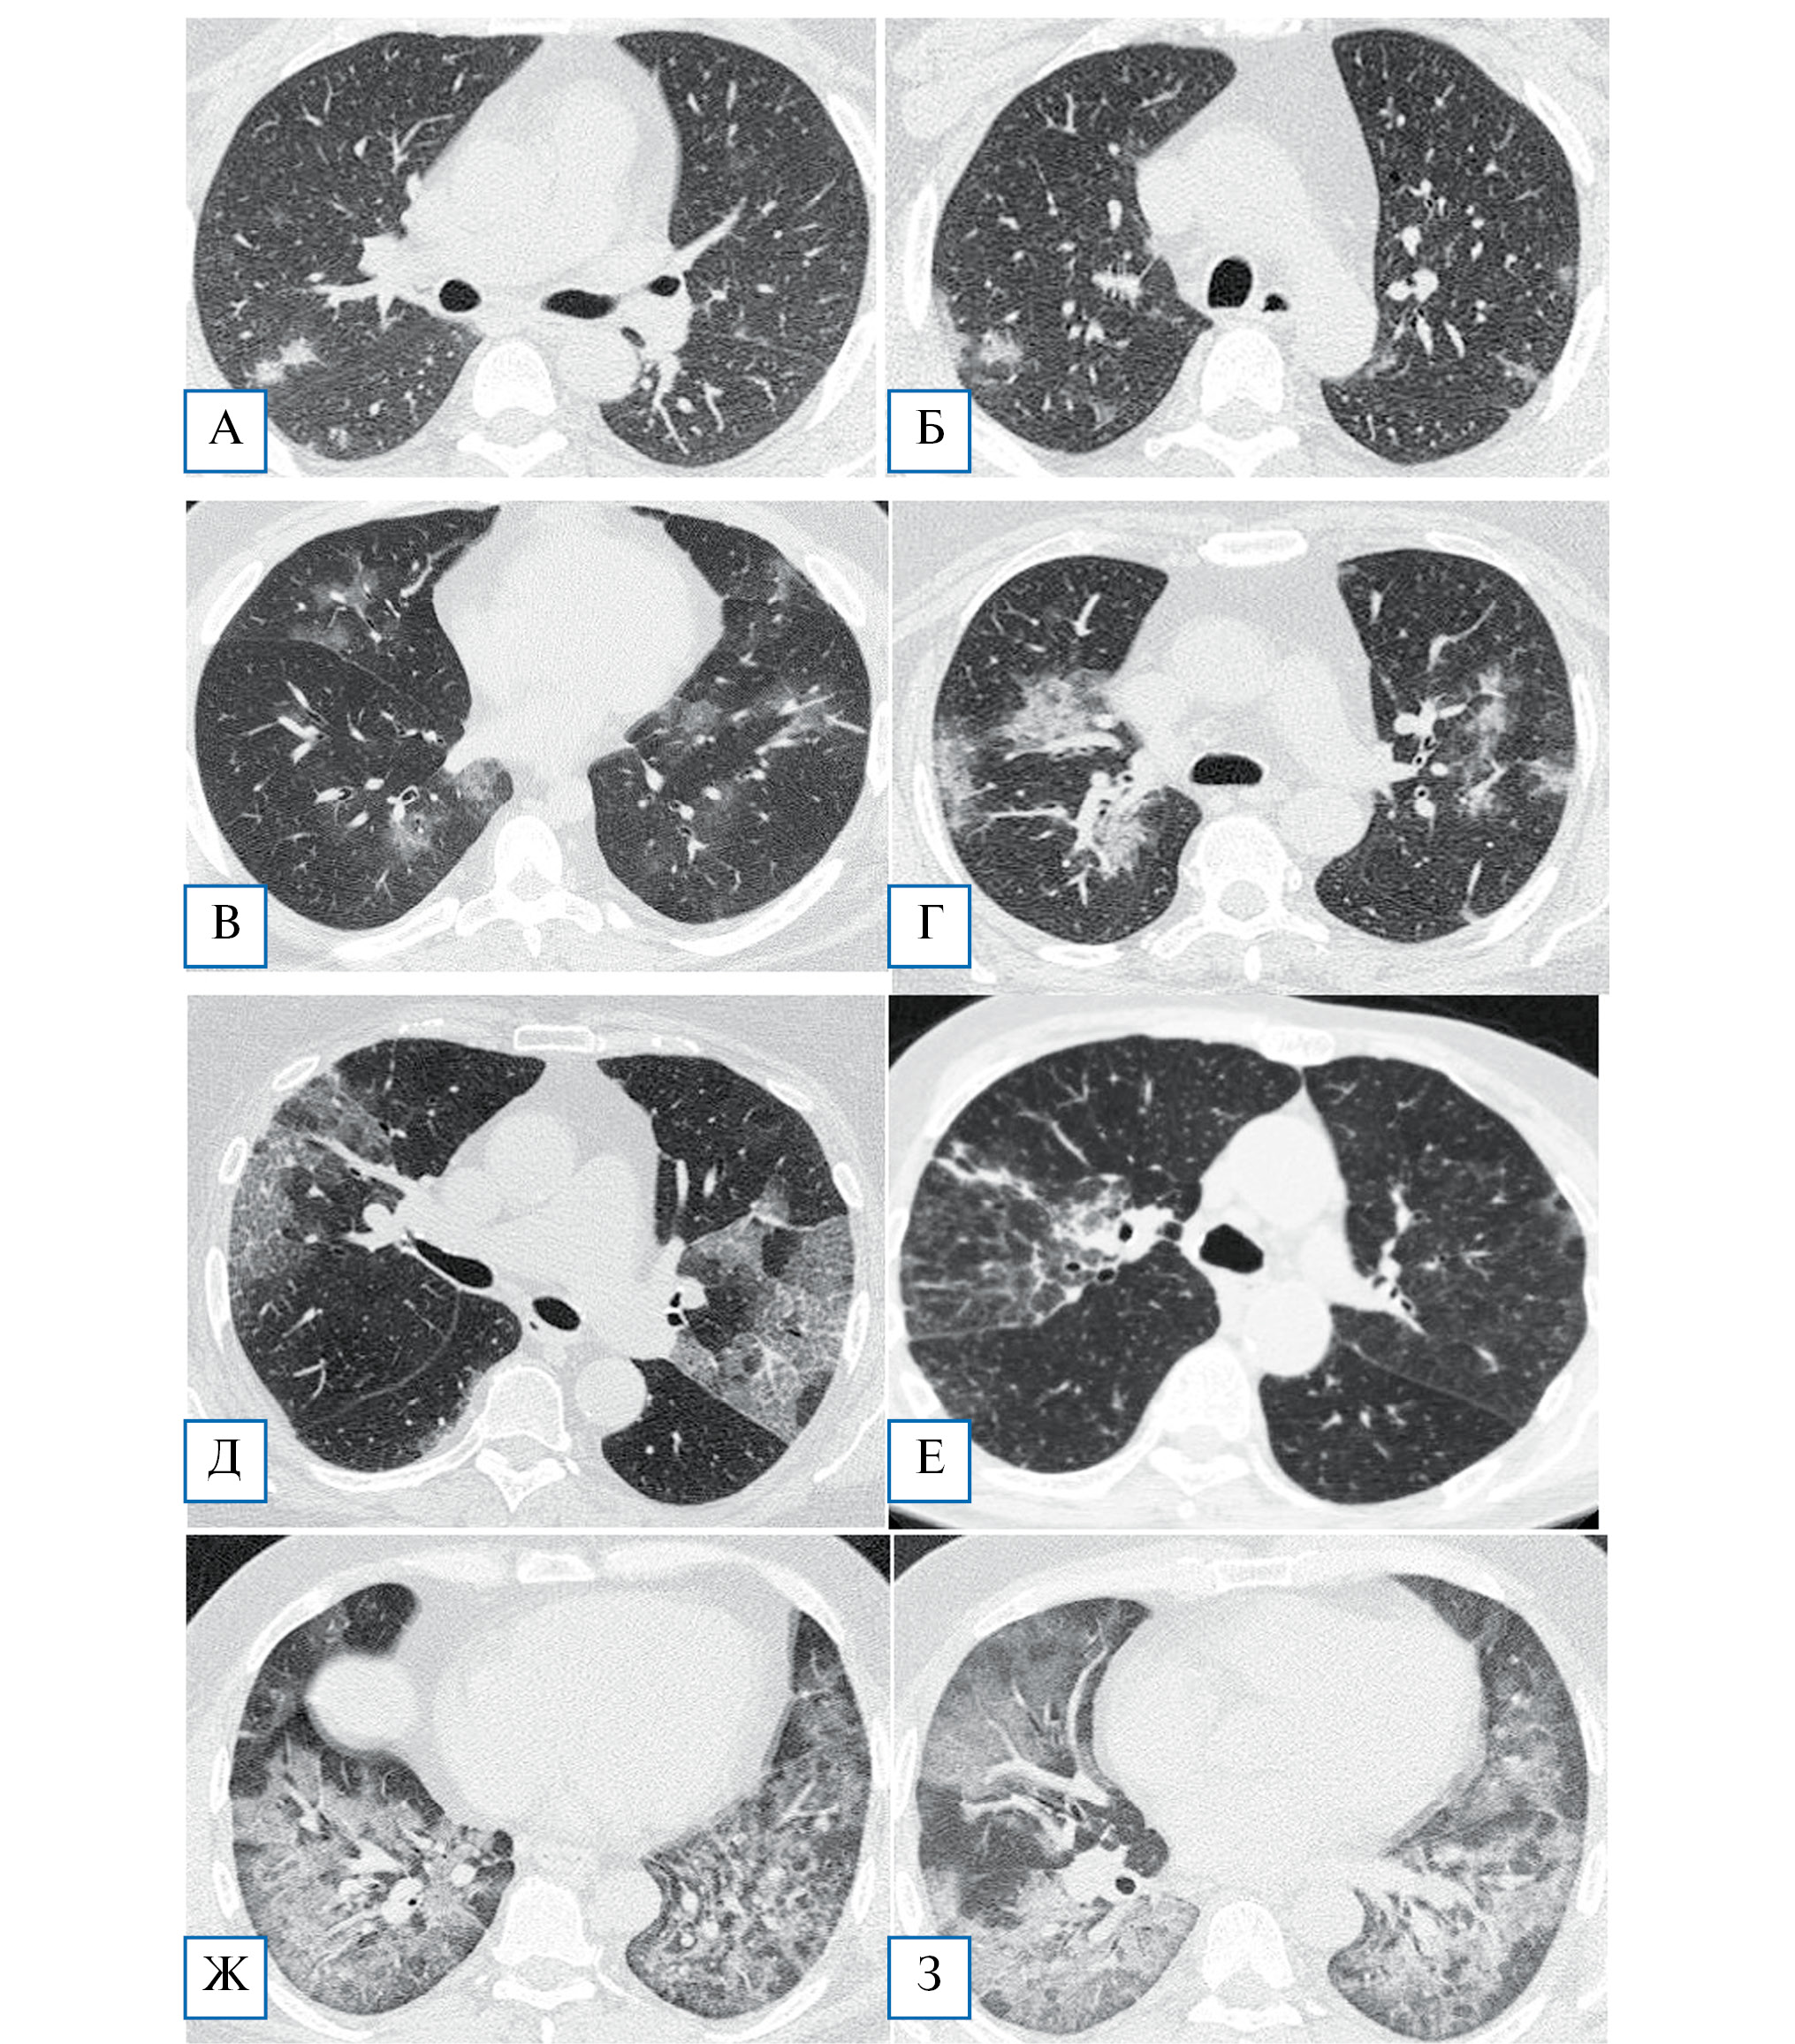

Компьютерная томография (КТ). Решающее значение в инструментальной диагностике COVID-19 (как для выявления пневмонии, так и для мониторинга эффективности терапии) имеет КТ органов грудной клетки. При технической возможности настоятельно рекомендуется проводить КТ высокого разрешения. Рекомендуется проводить исследование в день госпитализации; повторное исследование показано при прогрессирующем течении заболевании и подозрении на развитие осложнений [5, 6]. На ранних стадиях пневмонии COVID-19 часто обнаруживаются множественные субплевральные фокусы уплотнения по типу «матового стекла», а также фокусы, расположенные перибронховаскулярно (рис. 1, А, Б). В некоторых случаях в толще «матового стекла» наблюдаются утолщения междольковых перегородок и междолькового интерстиция, визуализируемые как рисунок «булыжной мостовой». В небольшом числе случаев могут обнаруживаться солитарные локальные тени либо очажки, распределенные вокруг бронхов. В случае прогрессирования заболевания внутри «матового стекла» появляются участки консолидации (рис. 1, В–Е), которые в критических случаях, в частности у больных острым респираторным дистресс-синдромом, захватывают большие зоны, преимущественно в базальных и субплевральных областях (рис. 1, Ж, З). По мере выздоровления обычно происходит полное исчезновение симптома «матового стекла», а в местах консолидации может формироваться интерстициальный фиброз.

Рис. 1. КТ-диагностика COVID-19

А, Б — начальная стадия заболевания: характерно появление немногочисленных, чаще субплеврально расположенных, небольшого размера лоскутных зон матового стекла; В — перибронховаскулярная локализация участков матового стекла; Г — появление зон консолидации (еще один характерный признак пневмоний, вызванных COVID-19); Д — распространенные двусторонние зоны матового стекла, довольно четко отграниченные от неизмененной легочной ткани, на фоне которых визуализируются ретикулярные изменения по типу утолщенных внутридольковых перегородок: картина напоминает КТ-симптомокомплекс, характерный для легочного альвеолярного протеиноза; Е — встречаются варианты преимущественного утолщения междольковых перегородок в пределах зон матового стекла; Ж, З — на поздних стадиях заболевания наблюдается трансформация всех зон матового стекла в участки консолидации, сливающиеся между собой. Преимущественная локализация изменений — базальные отделы нижних долей легких. КТ-данные из COVID-архива ФНКЦ ФМБА России.